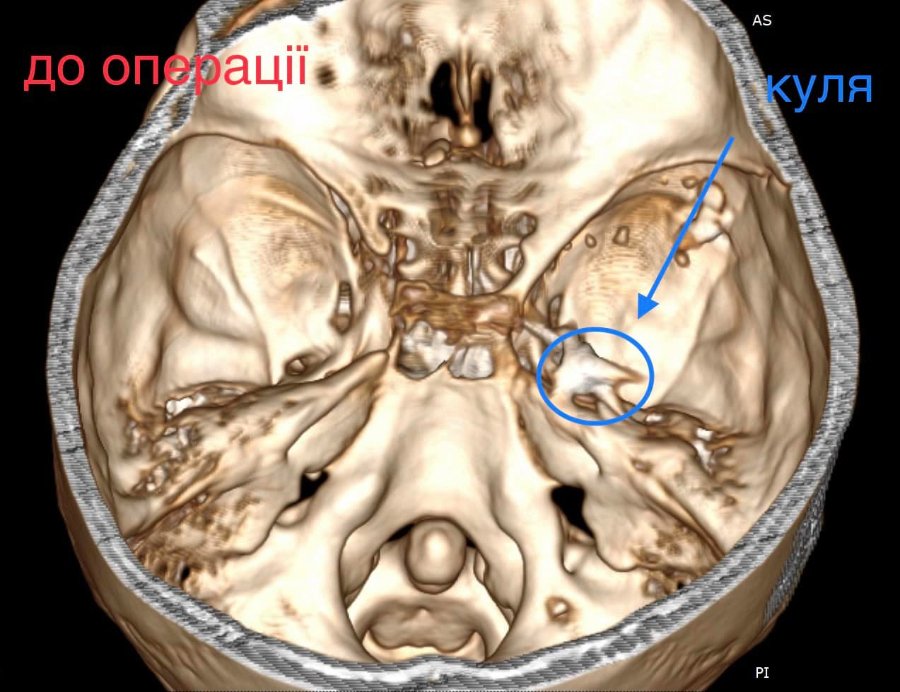

У Волинській обласній дитячій клінічній лікарні прооперували 16- річного юнака з травмою головного мозку. І травма ця дуже незвичайна – у хлопця була куля в голові, що призвела до руйнації скроневої кістки та частини головного мозку.

Лікарі виконали невідкладну операцію і вилучили стороннє тіло, видалили пошкоджені тканини і відновили цілісність збережених тканин.

«Добре, що куля зупинилась в 1 см від надзвичайно важливої судини і права скронева частка (яка пошкодилась в результаті травми) - функціонально незначима. Інакше, наш козак був би зовсім іншим, навзавжди», - пише лікар.